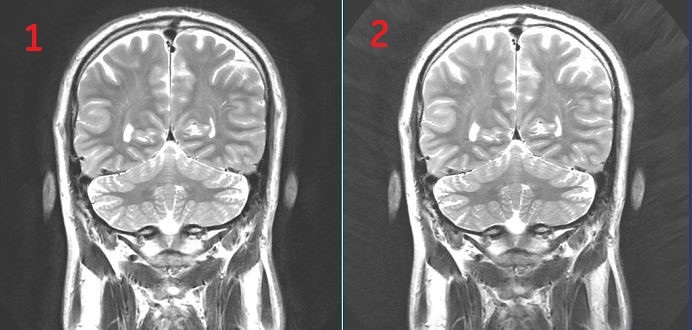

Figure 1. AIR Recon User CV on/off

Table 1. Image legend

NumberDescription

1AIR Recon turned ON. Note the improved image quality

2AIR Recon turned OFF.